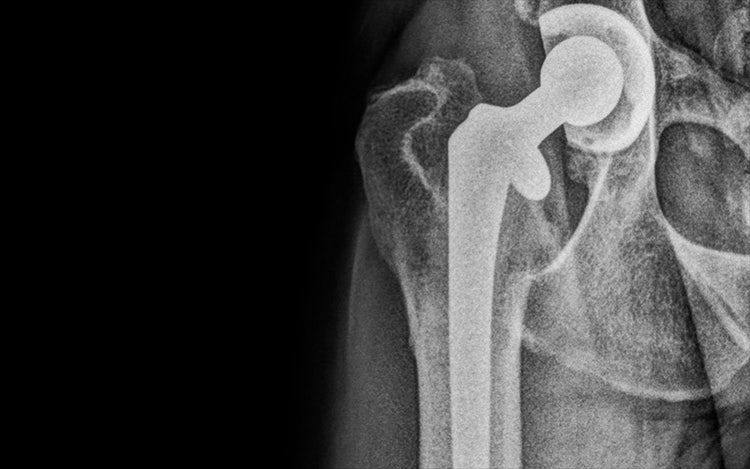

The initial step in total hip replacement is thorough examination of each dog’s specific radiographic morphology and accurate digital templating. Most total hip replacement systems have a 5-10 % complication rate, but this figure can be minimised with meticulous planning. In this German Shepherd’s case, a cemented total hip replacement system was thought to be most appropriate, due her morphology and age. An innovative new Biomedtrix total hip replacement system, with a highly cross-linked polyethylene acetabular liner with the incorporation of Vitamin E, was used in this case. This change to the acetabular prosthesis is designed to increase the longevity of the acetabular cup. In total, the surgery time took two hours.

Post operation, the patient was advised to have six weeks of strict rest and recuperation to minimise the potential risk of potential complication, particularly dislocation. At the end of this period, she was clinically assessed by David and her follow-up radiography shows no complication.